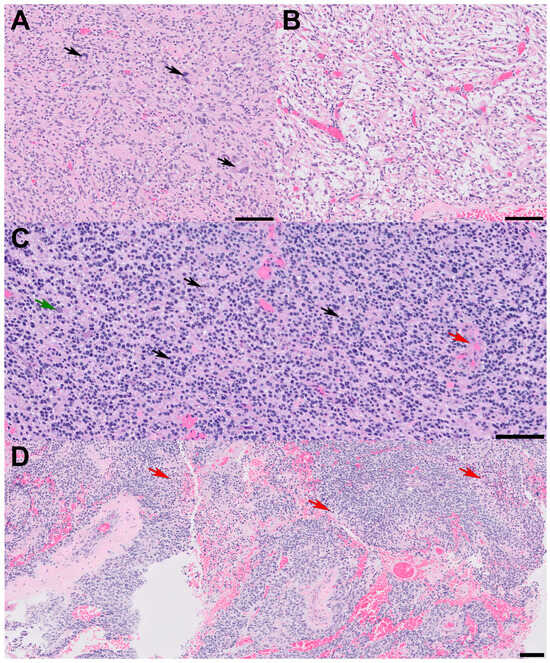

A 72-year-old male presented with a two-day history of altered mental status and emesis secondary to a 4.3 cm enhancing mass in the left temporal region, detected on a brain MRI with and without contrast (Figure 1A). His neurological exam was notable for memory impairment. Following a subtotal resection, which left a residual 1 cm nodule at the medial aspect of the resection cavity, histopathology revealed a high-grade glial neoplasm. In some areas, tumor cells with spindled hyperchromatic nuclei showed a compact growth pattern, interspersed with intervening areas (Figure 2A,B). Rosenthal fibers and eosinophilic granular bodies were absent. Scattered in these regions were bizarre, multinucleated cells with smudgy chromatin. In other areas, tumor cells with round-to-oval nuclei and scant-to-moderate amounts of cytoplasm were embedded in a fibrillary, neuropil-like background, associated with entrapped neurons, increased mitotic activity (at least 6 mitoses per 2 mm2), and incipient microvascular proliferation (Figure 2C). In these infiltrative high-grade areas, geographic necrosis and viable tumor cells surrounding vasculature formed a pseudopapillary architecture (Figure 2D). Tumor cells were positive for GFAP, OLIG2, and synaptophysin (weak, diffuse in high-grade areas, focal in compact areas). Neurofilament staining was negative in compact areas and highlighted entrapped axons in infiltrative high-grade areas. The p53 stain was patchy, suggestive of the wild-type TP53 gene. ATRX was retained in compact areas but was lost in infiltrative high-grade areas. P16 was absent from both regions. The Ki-67 labeling index was low in the compact areas but was estimated at 40% in high-grade areas (Figure 3).

Figure 2. Histopathologic features. All scale bars are 100 microns. (A) Sections reveal glial cells with spindled and hyperchromatic nuclei with a compact growth pattern and (B) intervening areas of the microcystic background. Note the pleomorphic, bizarre cells with smudgy chromatin in panel (A) (arrows); (C) in other areas, tumor cells with round nuclei and scant chromatin show infiltrative growth patterns and high-grade features. Note the entrapped cortical neuron (green arrow), mitotic figures (black arrows), and incipient microvascular proliferation (red arrow); (D) some high-grade areas show pseudopapillary architecture due to geographic necrosis (red arrows) and viable tumor cells clinging around vessels.

The patient was treated with radiation and concomitant temozolomide. Post-radiation brain MRI showed a stable residual 1 cm enhancing nodule at the medial aspect of the resection cavity (Figure 1B). At the time of publication, he completed 6 cycles of adjuvant temozolomide and remains stable both clinically and radiographically (Figure 1C). Ethical guidelines set out by the Declaration of Helsinki were followed in the preparation of this report, and the patient provided written consent.

Figure 1. Pre-surgical, post-surgical, and post-2 cycles of temozolomide imaging. (A) Pre-surgical axial T1 brain MRI with contrast reveals a 4.3 cm enhancing mass. (B) Post-radiation axial T1 brain MRI with contrast reveals a residual 1 cm enhancing nodule at the medial aspect of the resection cavity. (C) Following two cycles of adjuvant temozolomide, axial T1 brain MRI with contrast reveals a stable residual 1 cm enhancing nodule at the medial aspect of the resection cavity.